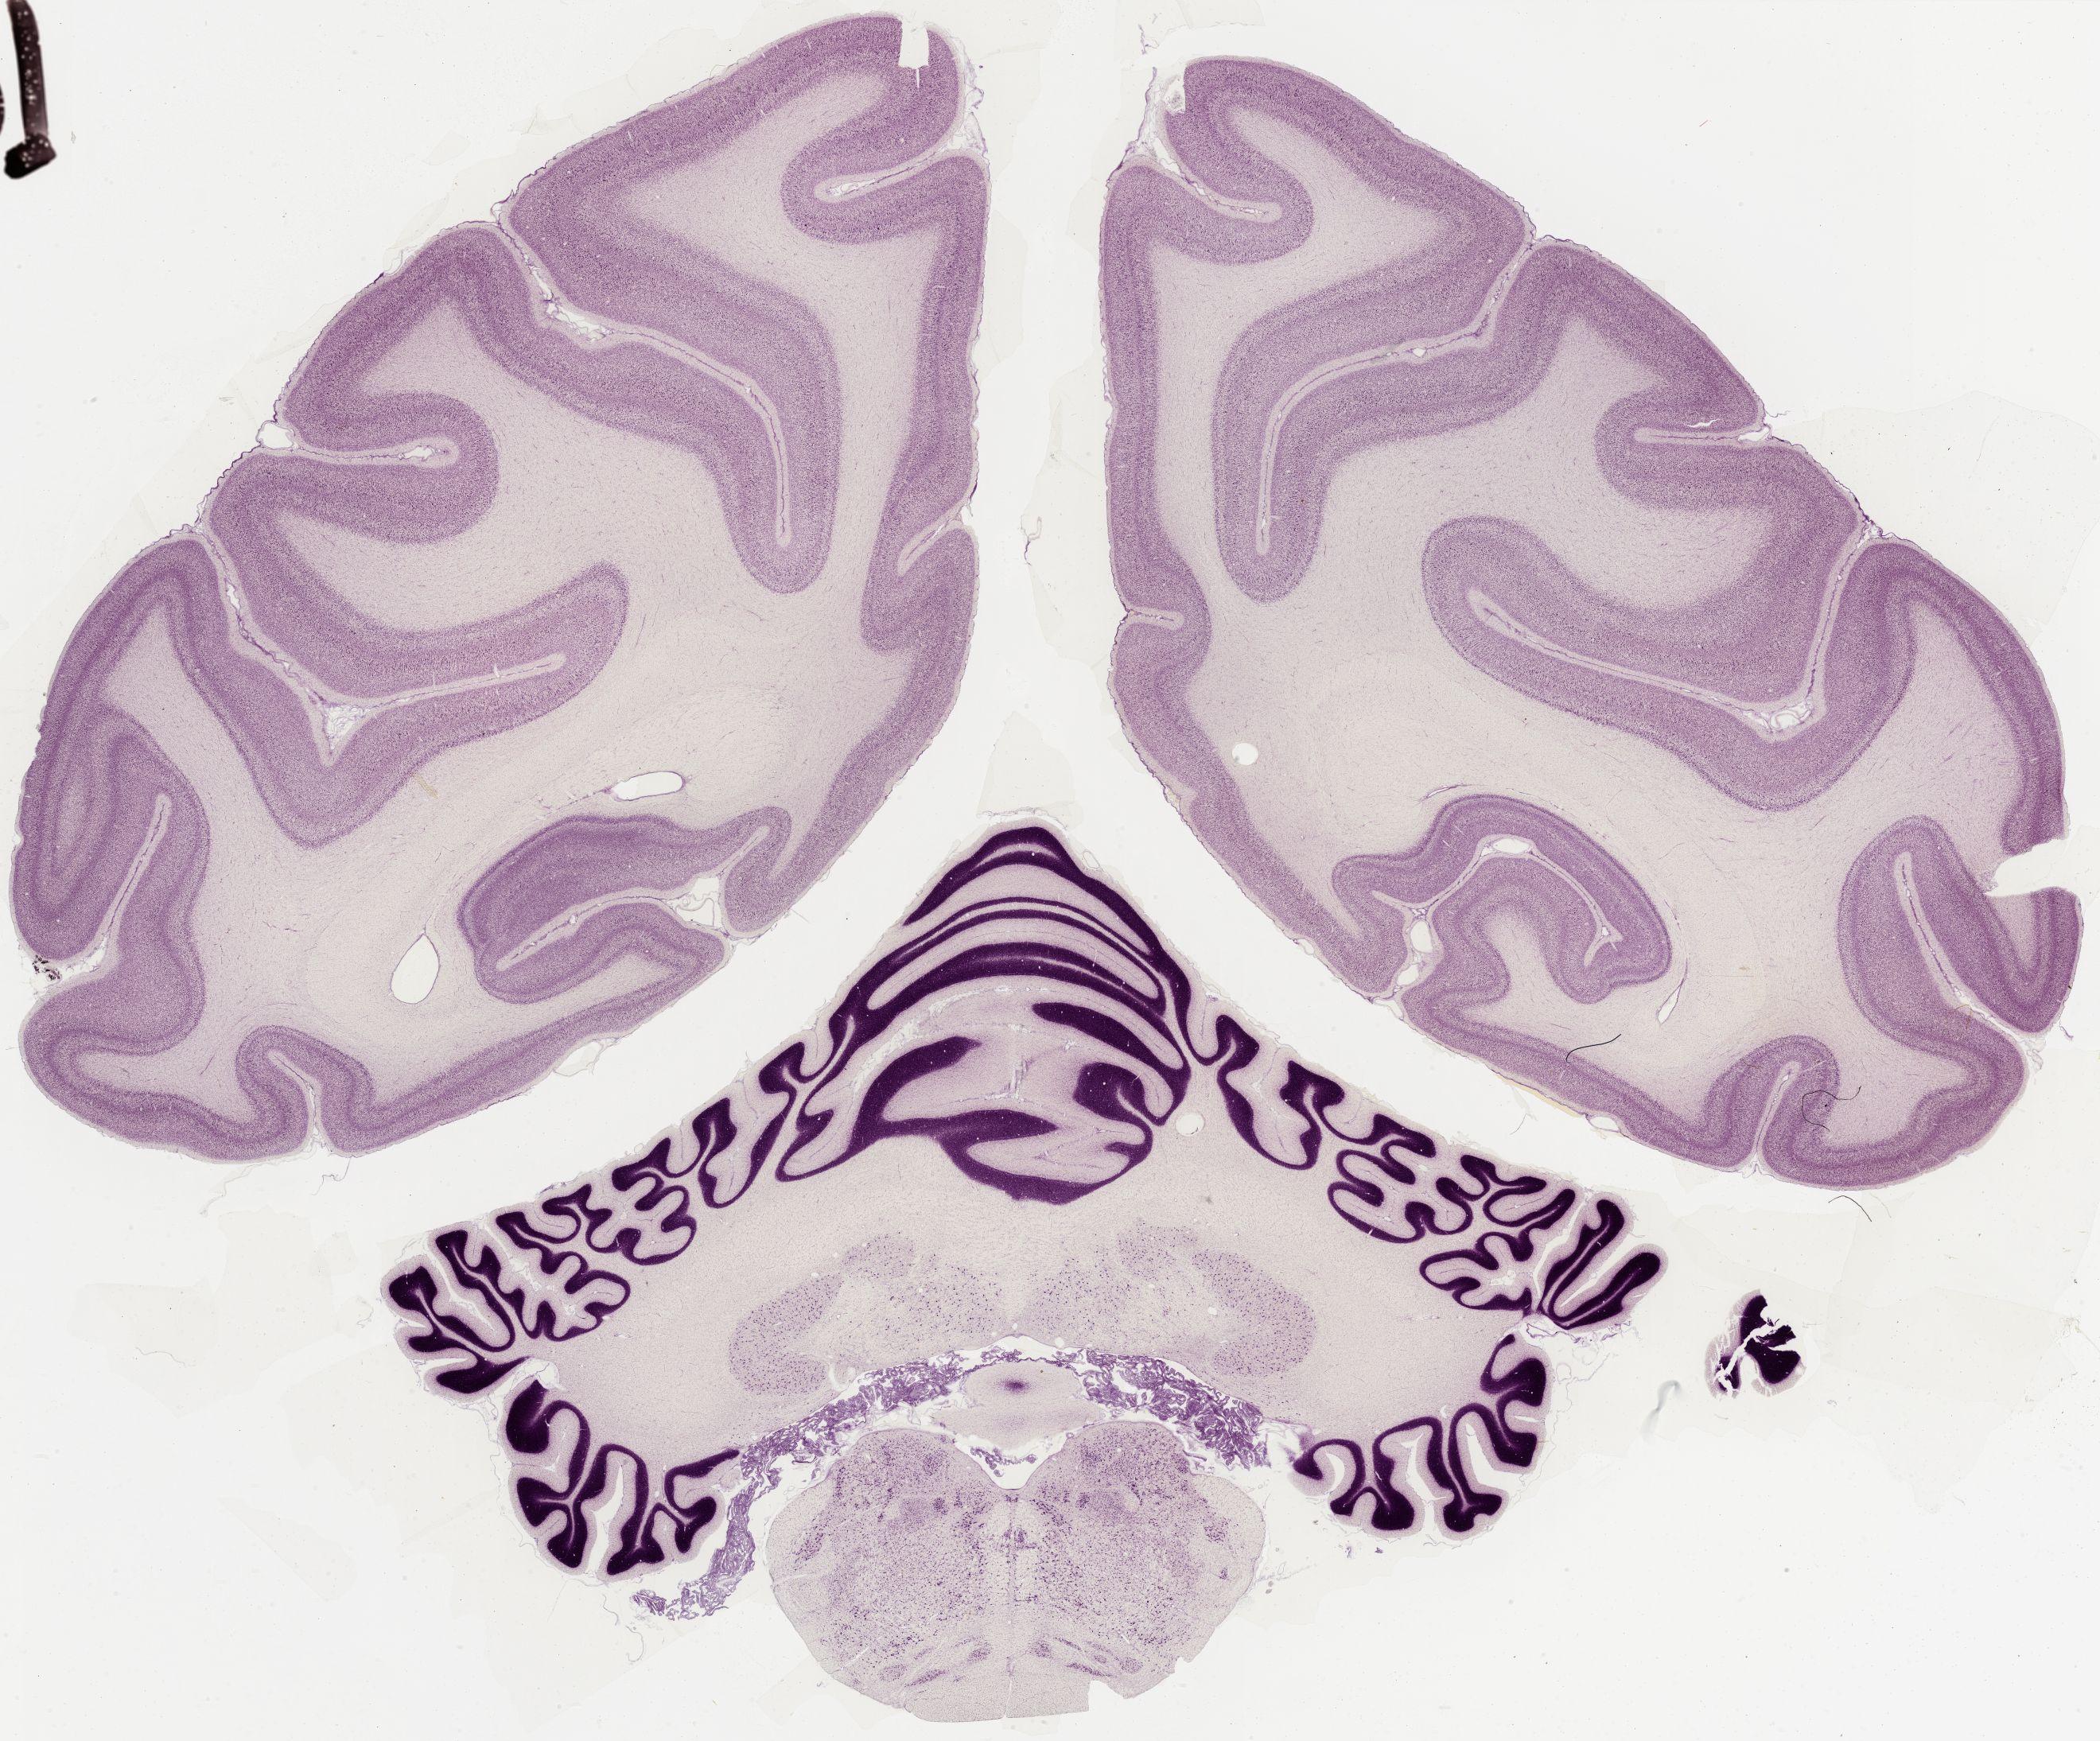

Datasets -> Macaca Mulatta -> Nissl, coronal, histo, Whole-Brain, adult

[ Metadata ]   ·   Source: Edward G. Jones

thumbnail

0582 - labeled